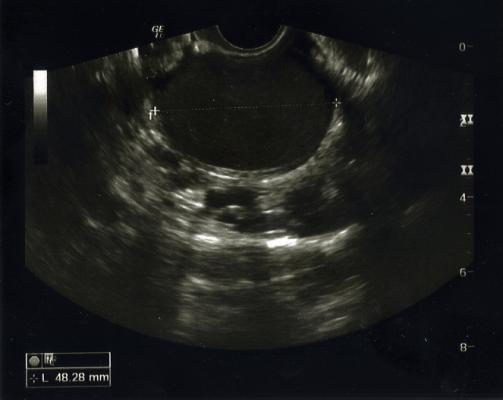

Ultrasound is usually the first-line imaging modality used when patients report chronic pelvic pain or have issues of infertility, both common symptoms of endometriosis, but few centers in the U.S. utilize ultrasound to screen for deep endometriosis. Existing scan protocol limitations and lack of awareness lead to suboptimal detection of deep endometriosis on pelvic ultrasounds.

Panel recommendations include transvaginal ultrasound of the posterior compartment, observation of the relative positioning of the uterus and ovaries, and the uterine sliding sign maneuver to improve the detection of endometriosis.